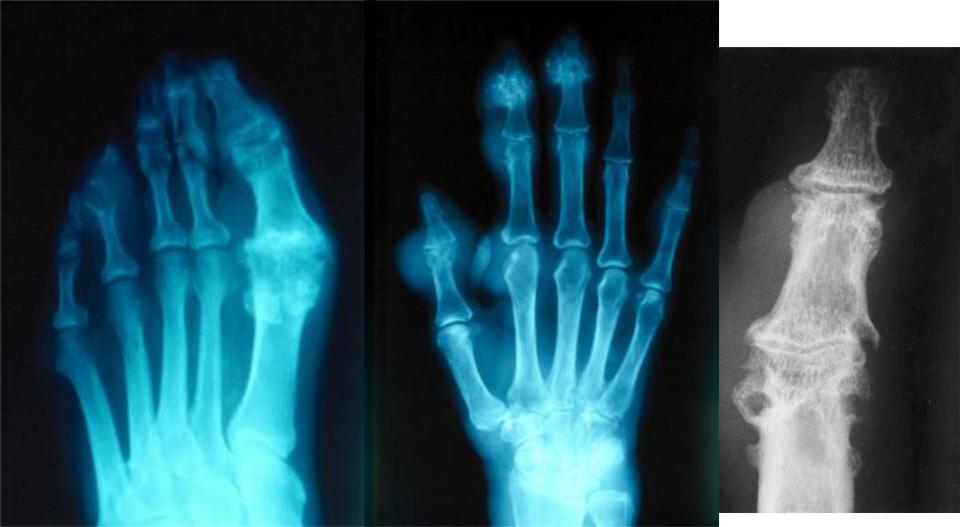

Рентгенография суставов

круглые “штампованные” дефекты эпифизов костей, окруженные склеротическойкаймой;

кистовидные дефекты, которые могут разрушать кортикальный слой кости

– симптом “пробойников”;

участки повышеннойплотностив мягкихтканях